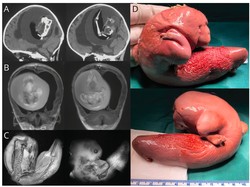

Salah satu bayi kembar berumur 5 bulan berinisial MS di Sinjai, Sulsel terlahir tanpa memiliki lubang anus. Orang tua bayi butuh biaya demi operasi anaknya.